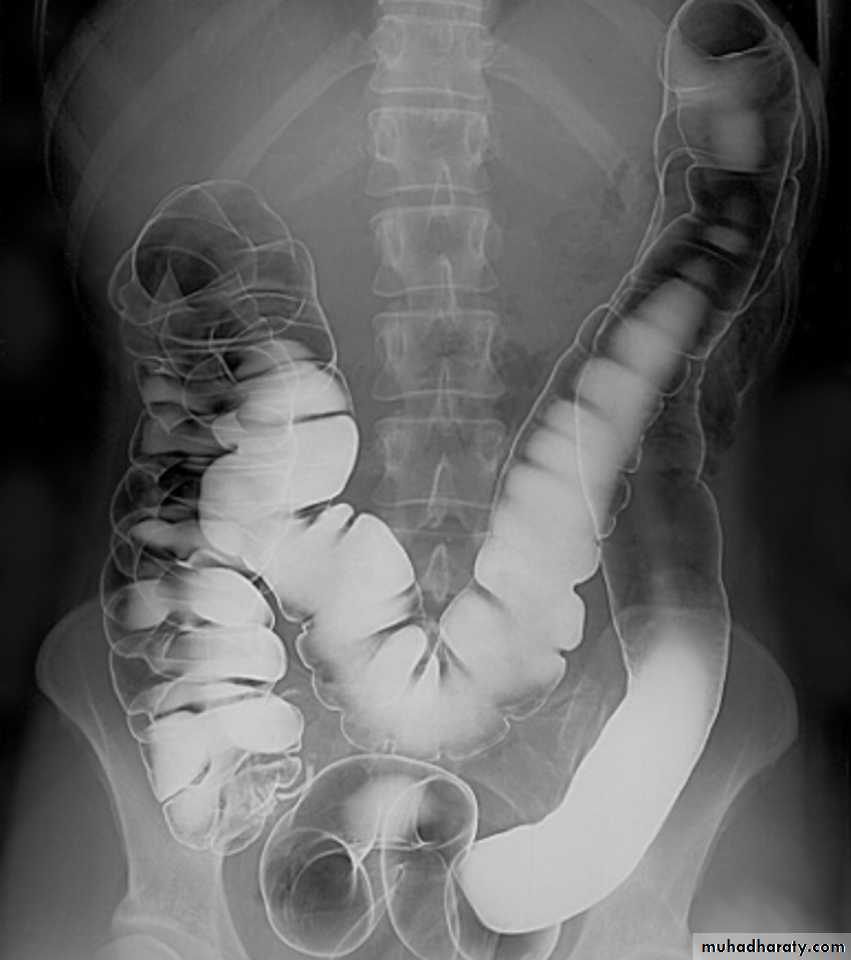

Barium enema

A: caecumB: ascending colon

C: transverse colon

D: descending colon

E: sigmoid colon

HF: hepatic flexure

SF: splenic flexure

F: terminal ileum